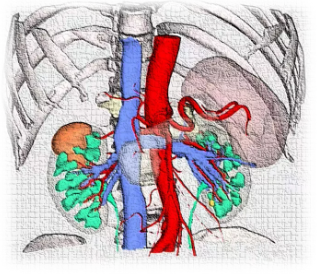

患者为一71岁男性,入院四个月前体检时发现右侧肾脏一占位性病变。入院后进一步行泌尿系增强CT提示恶性肿瘤可能性极大,如下图所示,肿瘤位于右肾中上部,与肝脏毗邻,右肾动脉前支前上段及前下段包绕肿瘤,而且右肾存在副肾,手术难度以及手术风险也随之增加,一旦肾脏动脉破裂出血,肾脏全切术不可避免,将严重影响生活质量。